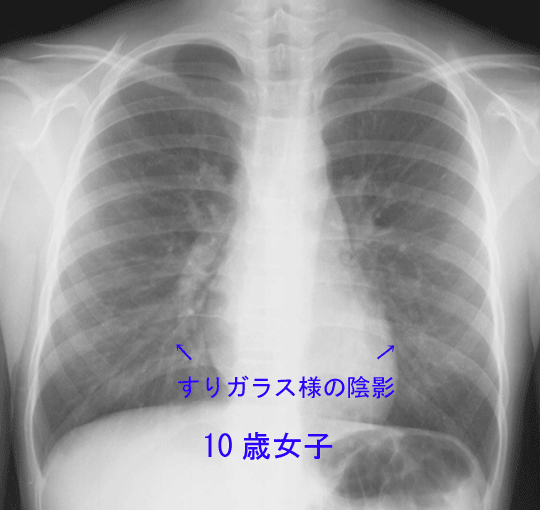

| 【感染症ニュース】マイコプラズマ肺炎流行拡大 感染すると咳が3〜4週間続くことも! 医師「過去最大の流行の恐れも」 …14、高知・佐賀・長崎2.00が多くなっています。 ◆マイコプラズマ肺炎とは? マイコプラズマ肺炎は、肺炎マイコプラズマ(Mycoplasma pneu… (出典:感染症・予防接種ナビ) |